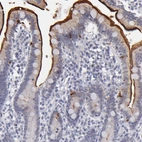

Immunohistochemistry analysis in human duodenum and skeletal muscle tissues using HPA002270 antibody. Corresponding MGAM RNA-seq data are presented for the same tissues.